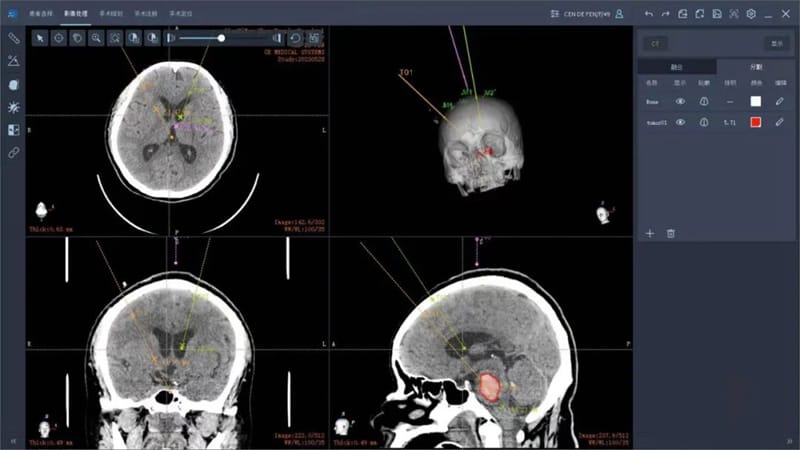

主任医师徐溥澄接诊后,对手术治疗方案进行讨论,考虑到常规开颅脑干血肿清除手术难度大、术后创伤大,经决定应用手术机器人行精准穿刺脑干血肿抽吸引流术;同时,考虑到患者中脑导水管受血肿推压,已出现脑积水征象,决定同时行侧脑室穿刺置管外引流术。

做好充分的术前准备,徐溥澄带领手术团队将CT及MRI影像数据传输到机器人导航系统中,进行融合重建,利用机器人导航系统合理规划手术路径。术中,依据机器人导航系统在机器人机械臂的引导下,经头皮穿刺完全抽出脑干血肿,精准避开了颅内大小血管及重要脑功能区。